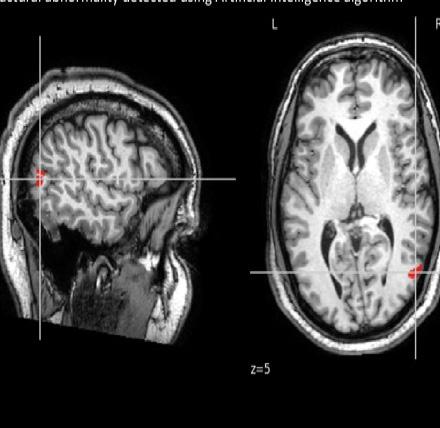

Photo courtesy of Dr Lawrence Binding, UCL

Epilepsy Research Institute & MRC Clinical Research Training Fellowship – Dr Oliver Davis University of Cambridge, awarded £270,458

DNA in our cells must be folded and stored correctly to give instructions to the cell and allow it to function properly. If not folded and stored properly, the DNA may not be able to instruct the cell about whether it should be stimulating or inhibiting electrical activity. This could be one of the reasons why people with epilepsy have too many stimulating cells and not enough inhibiting cells.

This study will investigate two genes that control DNA folding (called FOXG1 and CHD2). Using cells in a dish to model a brain, the team will investigate what impact turning off these genes has on DNA folding and if this influences the number of cells that inhibit electrical activity.

“The findings of this study could have strong scientific and medical implications for epilepsy. We will provide some much-needed insight into how genes with DNA-folding functions control how our brains develop. This will be important medically, as it opens up the possibility that DNA misfolding is a mechanism for how some forms of epilepsy arise. Critically, this will provide new targets for scientists to design diagnostic tests or drugs for treatments, which could really help to improve the care for patients with hard-to-treat forms of epilepsy.”

Dr Oliver Davis